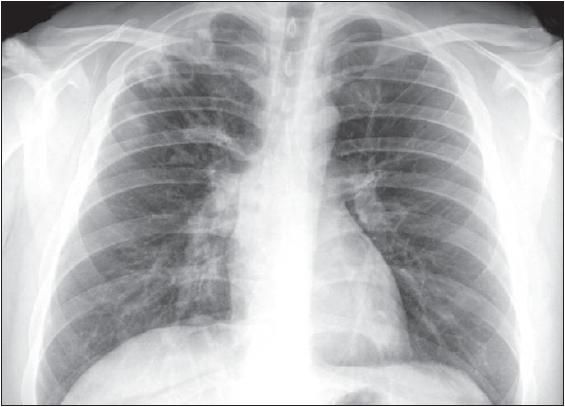

A chest radiograph revealed multiple cavitary lesions in the right upper lobe (Figure 1). A subsequent CT scan of the chest revealed multiple patchy areas of consolidation with cavitation most notable in the right lung (Figure 2A).

Figure 1 – Multiple cavitary lesions appear in the right upper lobe. This chest radiograph was obtained from a 26-year-old man who presented with cough and pleuritic chest pain.